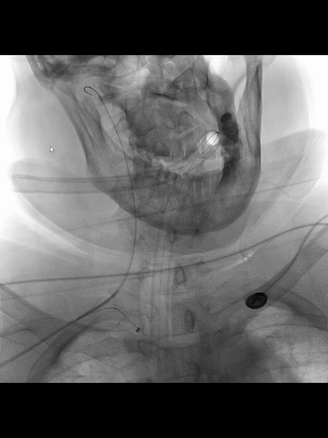

右股动脉穿刺置8F短鞘,5F长多功能管(125cm)和6F长鞘(90cm,Cook)组成同轴,导丝导引下5F管头端进入右锁骨下动脉。

长鞘跟进到右锁骨下动脉近端。

5F管沿导丝送至右腋动脉,经此管送入一.018"导丝(Command 18),其头端置于右肱动脉远端,保留导丝,交换出5F管,.018"导丝作悬吊支撑用。

微导管(Rebar 18)配合微导丝(Command 14)尝试超选右椎动脉,但微导丝头端难以通过V1的曲折管腔;后长鞘内衬一4F长多功能管增强支撑和指向性,但微导丝仍然难以克服右V1的曲折。

微导丝头端改塑形状后,还是克服不了右V1曲折。

穿刺右桡动脉,置入6F桡鞘;4F长多功能管(125cm)和Navien 072(105cm)组成同轴,泥鳅导丝导引下,4F管头端行至右锁骨下动脉近端。